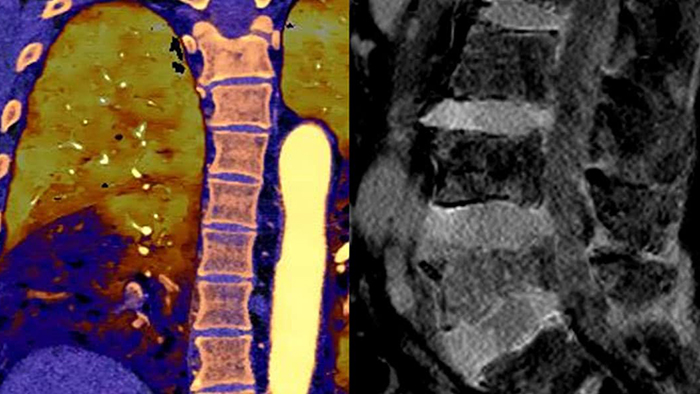

Observez la différence entre le scanner à détection spectrale et le scanner classique

Découvrez les avantages du scanner à détection spectrale